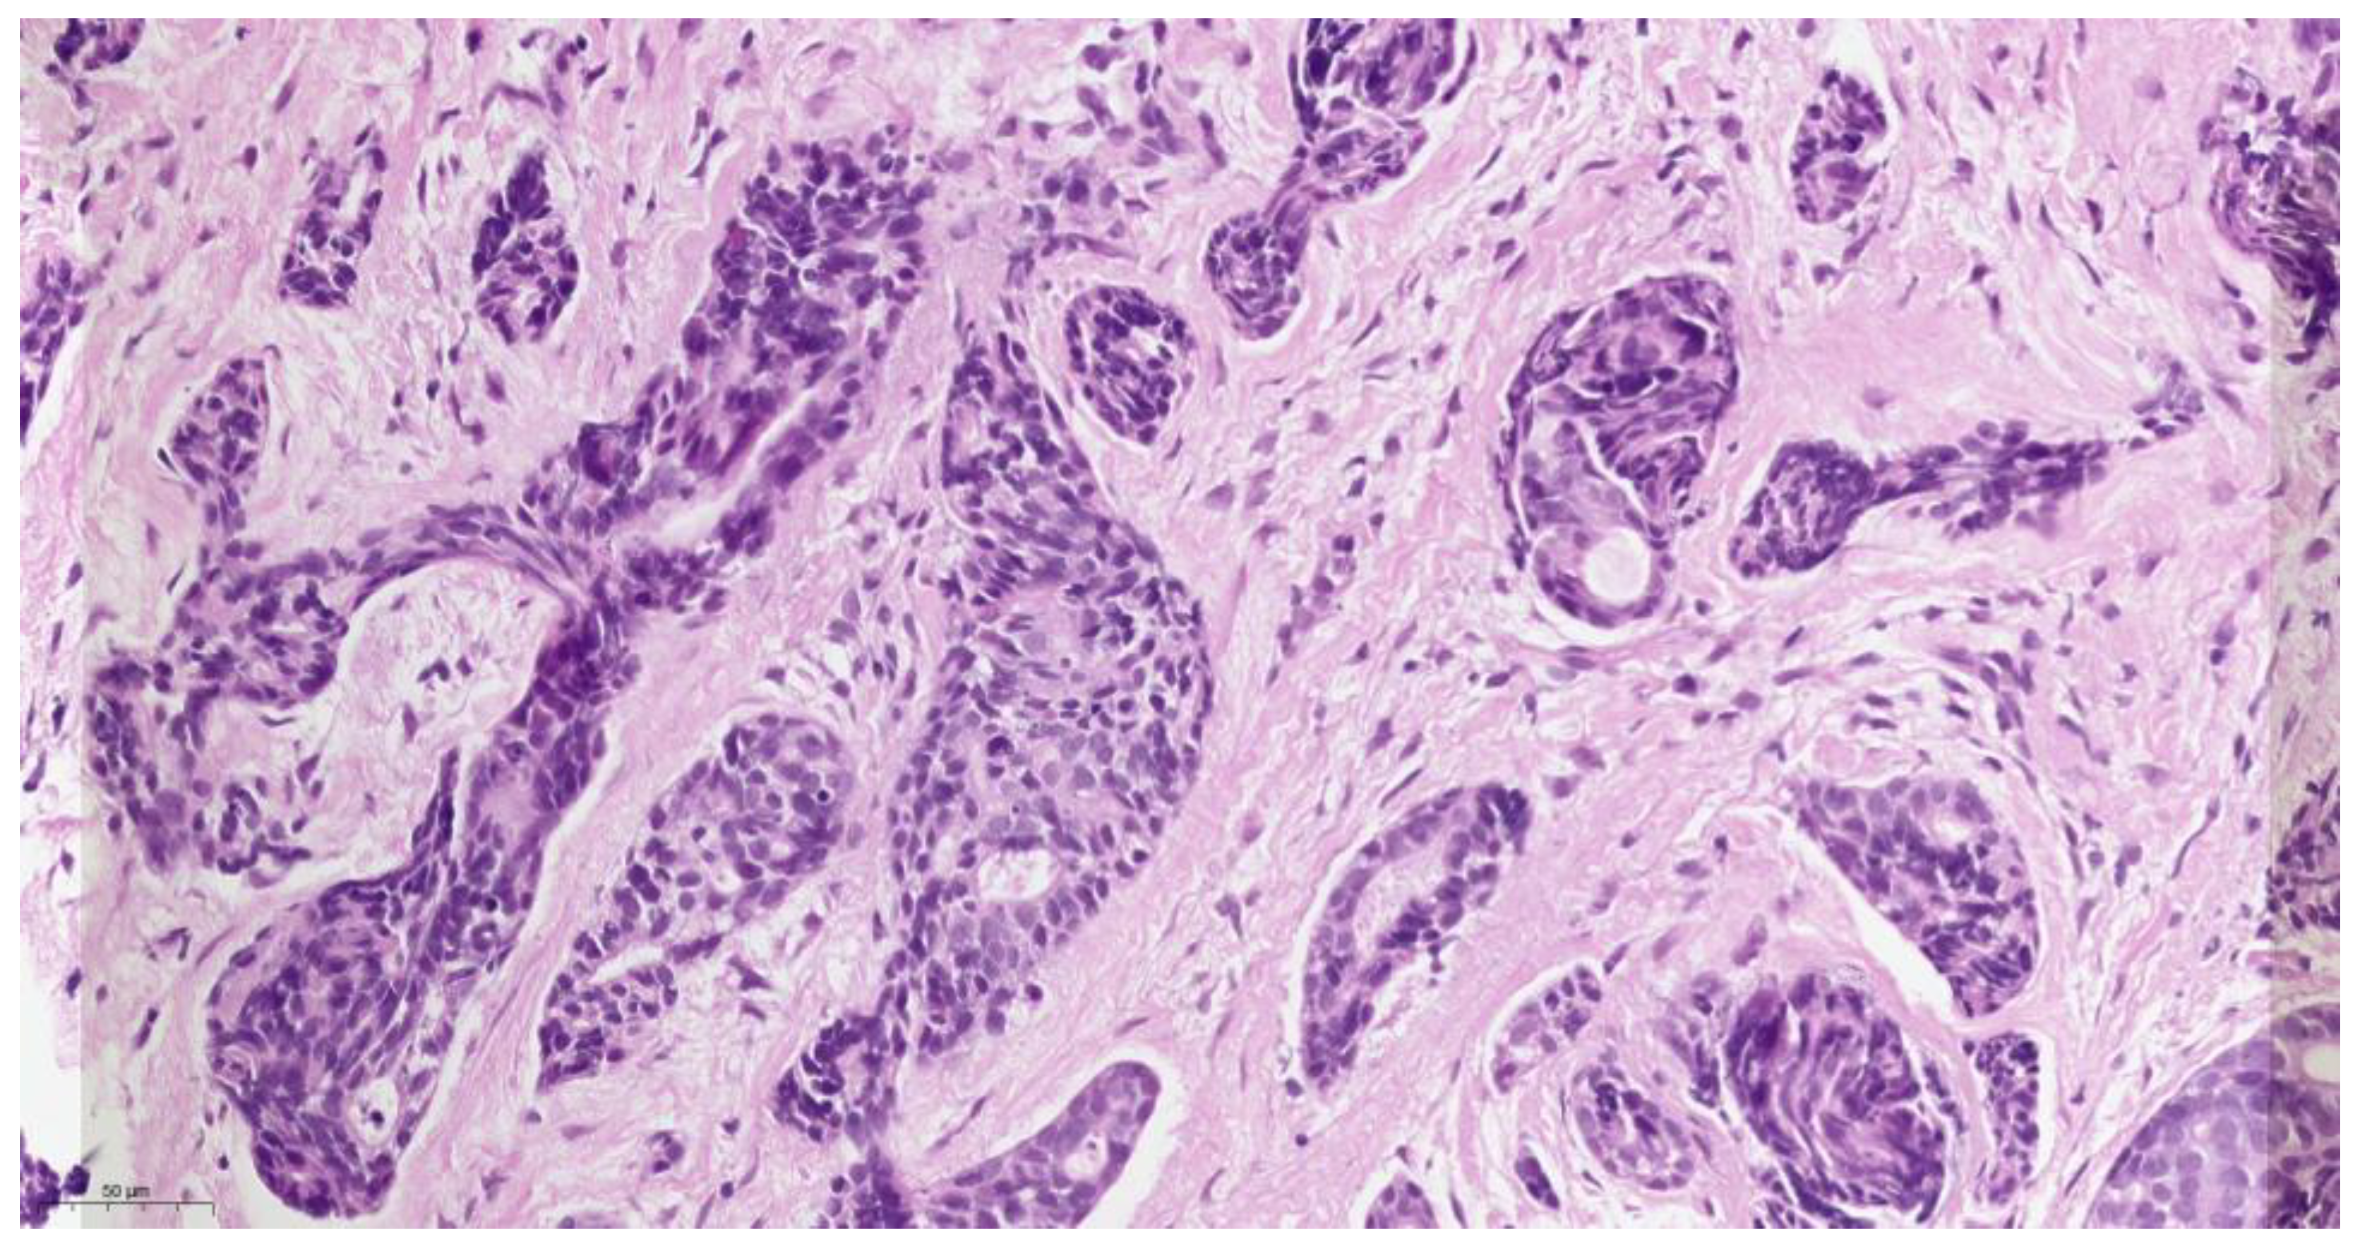

Histopathological examination (Figure 3) of the biopsied tissue indicated the diagnosis of cystic adenoid carcinoma, with the presence of glandular, cribriform, and predominantly solid growth patterns. The tumor is composed of small, rounded cells with a small amount of cytoplasm, basophilic staining, and a large, rounded nucleus with a small nucleus. The stroma of the tumor is desmoplastic, which means that there is an overgrowth of fibro-conjunctive tissue around the tumor.

Figure 3.

Hematoxylin-eosin staining of ACC, original magnification ×400.

The histopathology of ACC is characterized by a biphasic growth pattern, with a combination of solid, cribriform, and tubular structures. The tumor cells have a characteristic “Swiss cheese” appearance due to the presence of pseudocysts formed by tumor cells. The pseudocysts are lined by epithelial cells that secrete mucinous or hyaline material. The tumor cells are typically small and uniform in size, with scant cytoplasm and a round to oval nucleus. ACC has a tendency to invade surrounding tissues and can infiltrate nerves, blood vessels, and bone [13]. In our case, histopathological grading was predominantly solid. This indicates that the tumor had a solid growth pattern, with less evidence of the typical cribriform and tubular structures that are commonly seen in ACC. The solid growth pattern of ACC was associated with a more aggressive clinical course and a higher risk of metastasis.